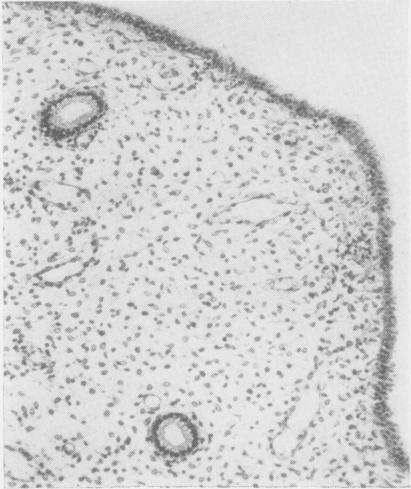

19-nor steroids in high and medium dosage in continuous or cyclic combined regimens with oestrogen produce an endometrium characterized by hyperinvoluted glands, a prominent predecidual reaction, suppressed arterioles, and dilated venules. When daily dosage is decreased to 2.0 mg. or less, the endometrium is composed of hyperinvoluted glands in an inert stroma; predecidual reactions are weak and infrequent; venules are rarely dilated, but spiral arterioles are suppressed.17-alpha-Acetoxyprogesterone derivatives in high and medium dosage given in a cyclic combined regimen with oestrogen produce similar but less intense effects to the 19-nor steroids. When given in cyclic sequential regimen, they produce an early secretory endometrium closely resembling normal patterns, chronologically retarded by about five days; in some instances a regressing, undatable secretory pattern is found, but predecidual response is minimal, and dilated venules are not seen.19-nor steroids in medium dosage given for 20 days without added oestrogen produce a late secretory endometrium with unpredictable variation from patient to patient and even from site to site within the same endometrium. Inhibition of the development of spiral arterioles is a common denominator in all progestagenoestrogen regimens. Modification of this element within the target tissue may be decisive for the morphogenesis of later vascular and stromal changes. Using synthetic progestagen-oestrogen regimens, endometrial gland secretion appears only after progestagen, whether given ab initio concomitantly with oestrogen or begun after a phase of oestrogen priming. Secretory vacuoles become evident about four to five days after progestagen is administered. The role of progestagen in secretion is interpreted as an indirect effect whereas its role in the development of decidual-like changes is construed as direct.

19-去甲甾体类药物以高剂量和中等剂量与雌激素连续或周期性联合使用时,会使子宫内膜呈现出以下特征:腺体过度退化、明显的蜕膜前反应、小动脉受抑制以及小静脉扩张。当每日剂量降至2.0毫克或更低时,子宫内膜由处于惰性基质中的过度退化腺体组成;蜕膜前反应微弱且不常见;小静脉很少扩张,但螺旋小动脉受到抑制。17-α-乙酰氧基孕酮衍生物以高剂量和中等剂量与雌激素周期性联合使用时,会产生与19-去甲甾体类药物相似但程度较轻的效果。当以周期性序贯方案给药时,它们会产生一种早期分泌期子宫内膜,与正常模式非常相似,但时间上延迟约五天;在某些情况下,会发现一种退行性、无法确定日期的分泌模式,但蜕膜前反应极小,且未见小静脉扩张。19-去甲甾体类药物以中等剂量连续20天给药且不添加雌激素时,会产生晚期分泌期子宫内膜,不同患者之间甚至同一子宫内膜内不同部位之间都存在不可预测的差异。抑制螺旋小动脉的发育是所有孕激素-雌激素方案的共同特征。在靶组织内对这一要素的改变可能对后期血管和基质变化的形态发生起决定性作用。使用合成孕激素-雌激素方案时,无论孕激素是一开始就与雌激素同时给药,还是在雌激素预处理阶段之后开始给药,子宫内膜腺体分泌都只会在给予孕激素之后出现。在给予孕激素约四到五天后,分泌空泡变得明显。孕激素在分泌中的作用被解释为间接作用,而其在蜕膜样变化发展中的作用则被认为是直接作用。